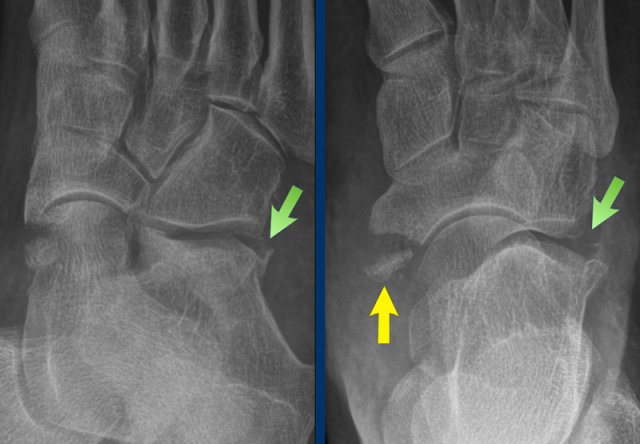

case 3 - distortion

The findings are:

• Avulsion of the medial pole of navicular bone

• Fracture on the lateral side of the calcaneus

This means that there is an injury to the Chopart's joint, which has an S-shape and is formed by the articulation of the calcaneus  with the cuboid and the articulation of the talus with the navicular.

In this case there was an eversion with distraction on the talonavicular side with an avulsion of the medial pole of navicular bone (yellow arrow) and compression on the calcaneocuboidal side leading to a nutcracker fracture (white arrow).